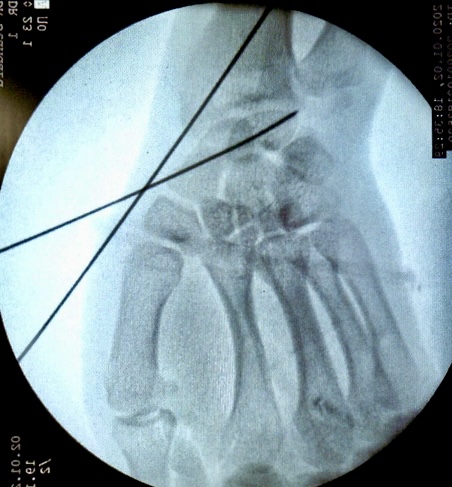

5)透视正侧位,调整导针位置,透视下见导针位置良好后用空心钻沿着导针钻孔,拧入螺钉,加压包扎伤口。

拧入空心螺钉